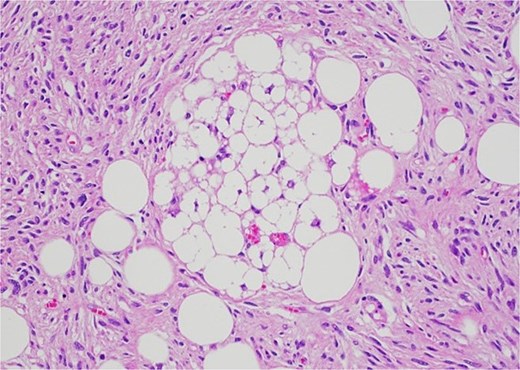

Histology revealed a multilobulated spindle cell lesion, with low- and high-grade areas, with an abrupt transition between these areas. There was an adjacent focus of adipose tissue with rare cytologic atypia suggestive of possible WDL, which indicated that the tumor mass may represent DDL. However, there was a single focus of lipoblasts identified, bringing up the differential of pleomorphic liposarcoma. Therefore, in situ hybridisation was performed and showed MDM2 amplification, which confirmed the diagnosis of DDL, with likely homologous lipoblastic morphology. The tumour was excised with clear margins (Figs 3–8).

The high-grade component demonstrates increased cellularity, hyperchromasia and moderate to marked pleomorphism including scattered multinucleate cells.